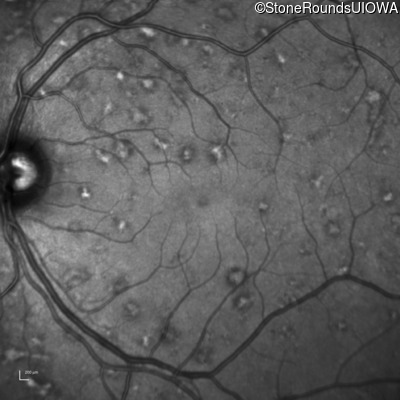

Infrared Fundus Photograph - Right - 20/15 sc

Exemplar